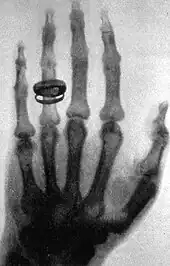

Le premier cliché célèbre est celui de la main d'Anna Bertha Röntgen réalisé le [4] (pose de 25 minutes) ; il s'agit de la première radiographie. Un mois plus tard, Jean-Alban Bergonié reproduit à Bordeaux l'expérience de Röntgen, avant que ce dernier publie officiellement.[réf. nécessaire]

En 2003, le magazine Life a inclus la radiographie de la main de l’épouse de Röntgen parmi les « 100 photographies qui ont changé le monde »[28].